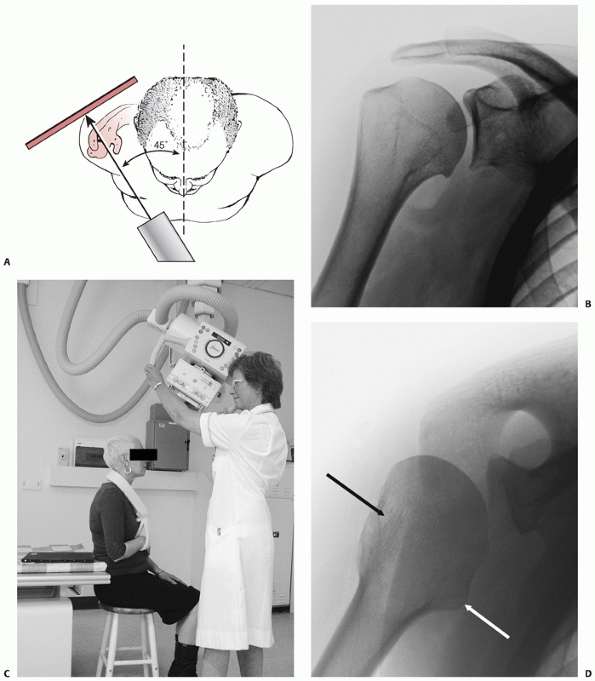

consists of anteroposterior and lateral radiographs, together with an

axillary view. The latter may be uncomfortable to obtain after injury,

and the Velpeau view79 or modified axillary view302 are considered acceptable substitutes, because these can be taken without removing the painful fractured arm from the sling (Fig. 35-6).

FIGURE 35-6 A. The true anteroposterior view of glenohumeral joint requires the beam to be angled 45 degrees from the sagittal plane. B.

The true anteroposterior view in the plane of the scapula is orthogonal to the face of the glenoid to show the maximum amount of the humeral head articular surface possible. C. The modified axial view is obtained with the arm resting in a sling and the x-ray gantry tilted 45 degrees in the sagittal plane. D. The view clearly shows the outline of the greater tuberosity (black arrow) and lesser tuberosity (white arrow) and confirms congruent reduction of the humeral head. |